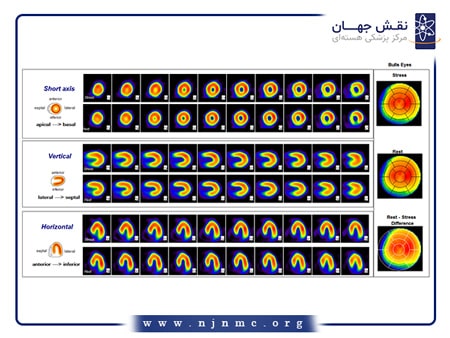

اسکن هسته ای قلب

اسکن هستهای قلب یک روش تصویربرداری تشخیصی میباشد که جریان خون به عضله قلب را ارزیابی میکند. این روش به تشخیص بیماری عروق کرونر (CAD) و ارزیابی ميزان بافت زنده عضله قلب پس از وقوع انفاركتوس کمک میکند. این آزمایش شامل تزریق یک ردیاب رادیواکتیو است که سپس توسط دستگاه مخصوص تصویربرداری میشود تا نشان دهد که خونرسانی به عضله قلب، در حالت استراحت و در هنگام استرس (ورزش یا ناشی از دارو)، به چه صورت میباشد.